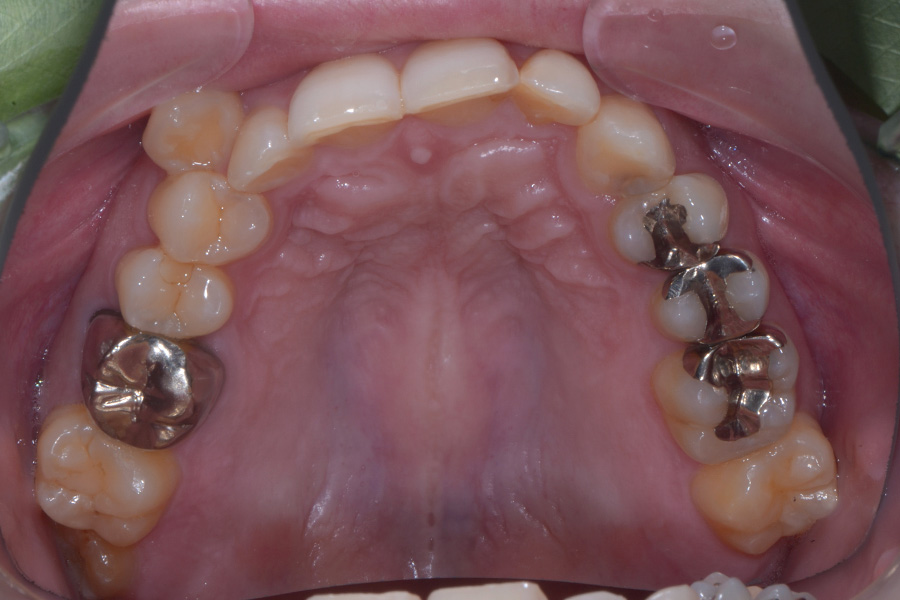

【30代男性】

八重歯を引っ込めたい

治療前

| 主訴 | 八重歯を引っ込めたい |

| 治療内容 | 上下顎ラビアル矯正(表側矯正) |